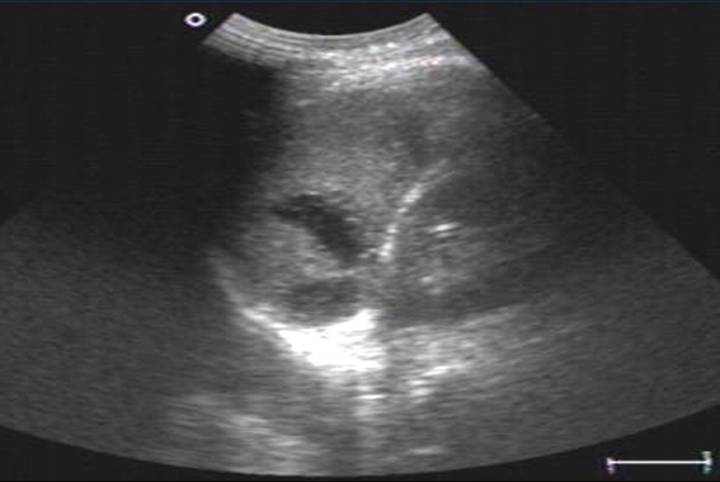

声像表现

1、脾大

2、急性期脾梗死

单发或多发,大小不一

单发者楔形,基底宽,凸面向包膜,尖端指向脾门

内部回声呈大片回声减低区

中央发生坏死液化出现无回声区

CDFI梗塞区缺乏血流灌注因而不显示彩色血流信号。